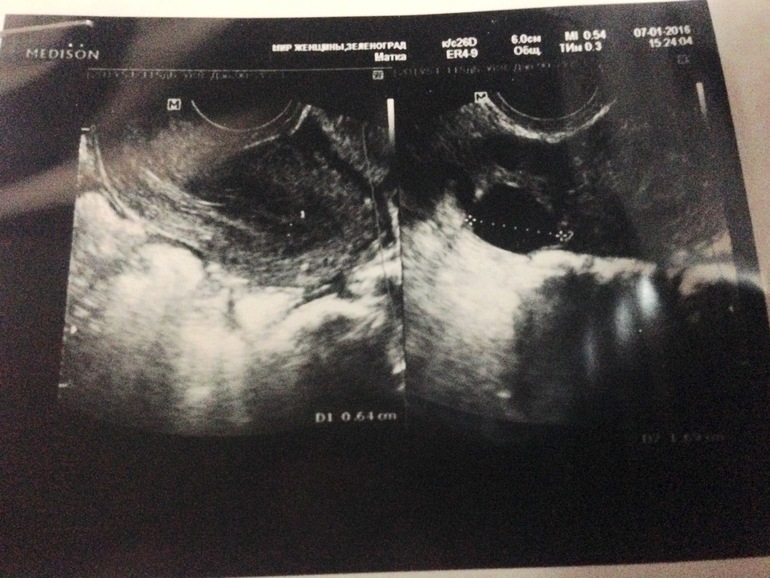

Может Вы не то сфотографировали? На фото явно не яичник, скорее матка (и сверху на фото написано матка). А справа виднеется кусочек фото, может там яичник?

О, вот это другое дело, справа видно яичник. Но сказать сложно....ДФ чёткой круглой формы, а ЖТ с неровными краями, в идеале звездчатой формы. Надо ещё ориентироваться на описание врача (размер, ИР), но, скорее, я сказала б, что больше похоже на ДФ с яйценосным бугорком и О вот-вот или ЖТ. Для ДФ немного кривовато...

Краснодар